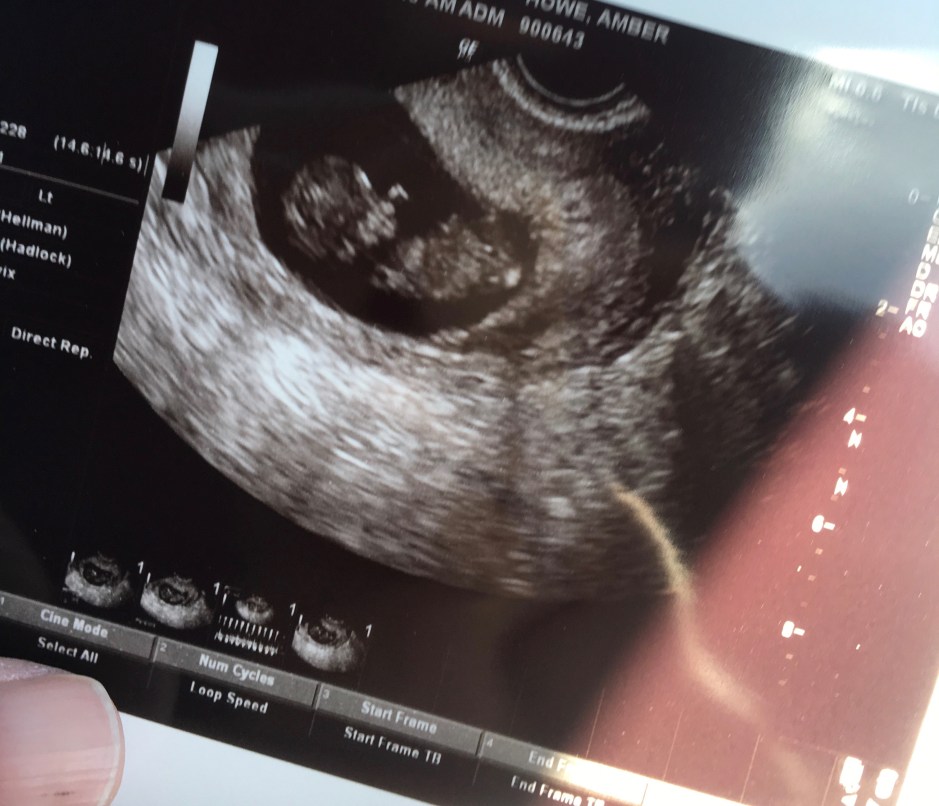

Because I spotted some left over in the bathroom, I took a pregnancy test on a whim one day, way before the official blood test was scheduled. I remember looking down at it as I applied makeup, blinking in disbelief at the faint second line on the test that meant it was positive. I drank a glass of water and took another test, thinking that one must be old or defective. There was that faint second line again. I went to the store and bought another brand of pregnancy test. There was no denying it- in the midst of the hardest time in my life, I was pregnant. The blood test confirmed the news and we were treated to multiple ultrasounds early on to see our little bean wiggling, its heartbeat chugging away! It’s hard to describe that feeling of excitement and joy that I felt, paired with an unfamiliar fear in my gut. All signs were pointing to the fact that this was the wrong time to add a baby to the family. I wasn’t healthy, physically or mentally. Looking back, I think I had an unspoken expectation that I would lose the baby in those first few months. Truly, John and I would exchange glances after each checkup, silently surprised that this little being was not only growing, but thriving! With each confirmation that the baby was healthy, more and more joy and excitement filled my heart.

Despite the amazing reality that we were going to be blessed with another family member, our struggles didn’t end, and neither did my depression. I did my best to hide it. A wonderful thing about being pregnant is that it encourages you to take good care of yourself. It wasn’t just about me anymore! I watched a bump develop far earlier than it did with Oden. I ate well and spent a lot of time outside with a rambunctious 2-year-old. I loved wearing summer dresses with a growing belly, something I didn’t get to experience with Oden. My children became my focus, even if the rest of my life was not so positive. My folks visited and helped sort through baby clothes and prepare the baby nursery. I squealed at the tiny baby clothes and daydreamed about baby names and watched this belly grow and grow (and grow). I cried tears of joy when we learned we were having another boy. I included Oden in everything I could and felt my heart swell when his little voice talked to “baby brudder” through my belly button. I was certainly trying to hold it all together- motherhood, pregnancy, supporting my husband during a trying time, staying optimistic about the future. But there was no denying the pit in my stomach that wouldn’t go away. My new baby worry list was already long, but as the months went by, I added “postpartum depression” to it.